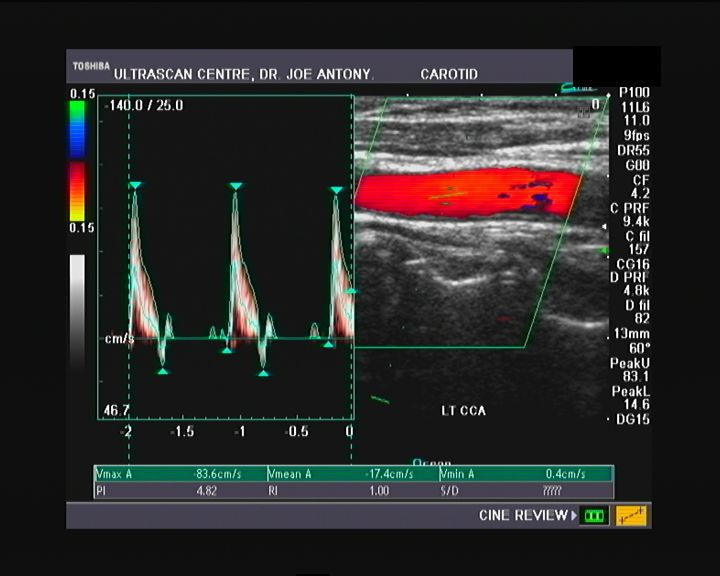

Spectral Doppler waveform of the normal Common carotid artery (CCA)

The above images (Rt. CCA) show moderately broad systolic peaks and moderate diastolic flow in diastole. The peak systolic velocity (PSV or V-max) is also in a range between that of the ICA and ECA. This is the typical appearance of the waveform of the CCA. Normal PSV for the CCA is usually less than 100cms./sec. (In this case, the PSV= 94 cms./sec.). The PSV in the CCA increases towards its proximal part (ie: towards the aorta).